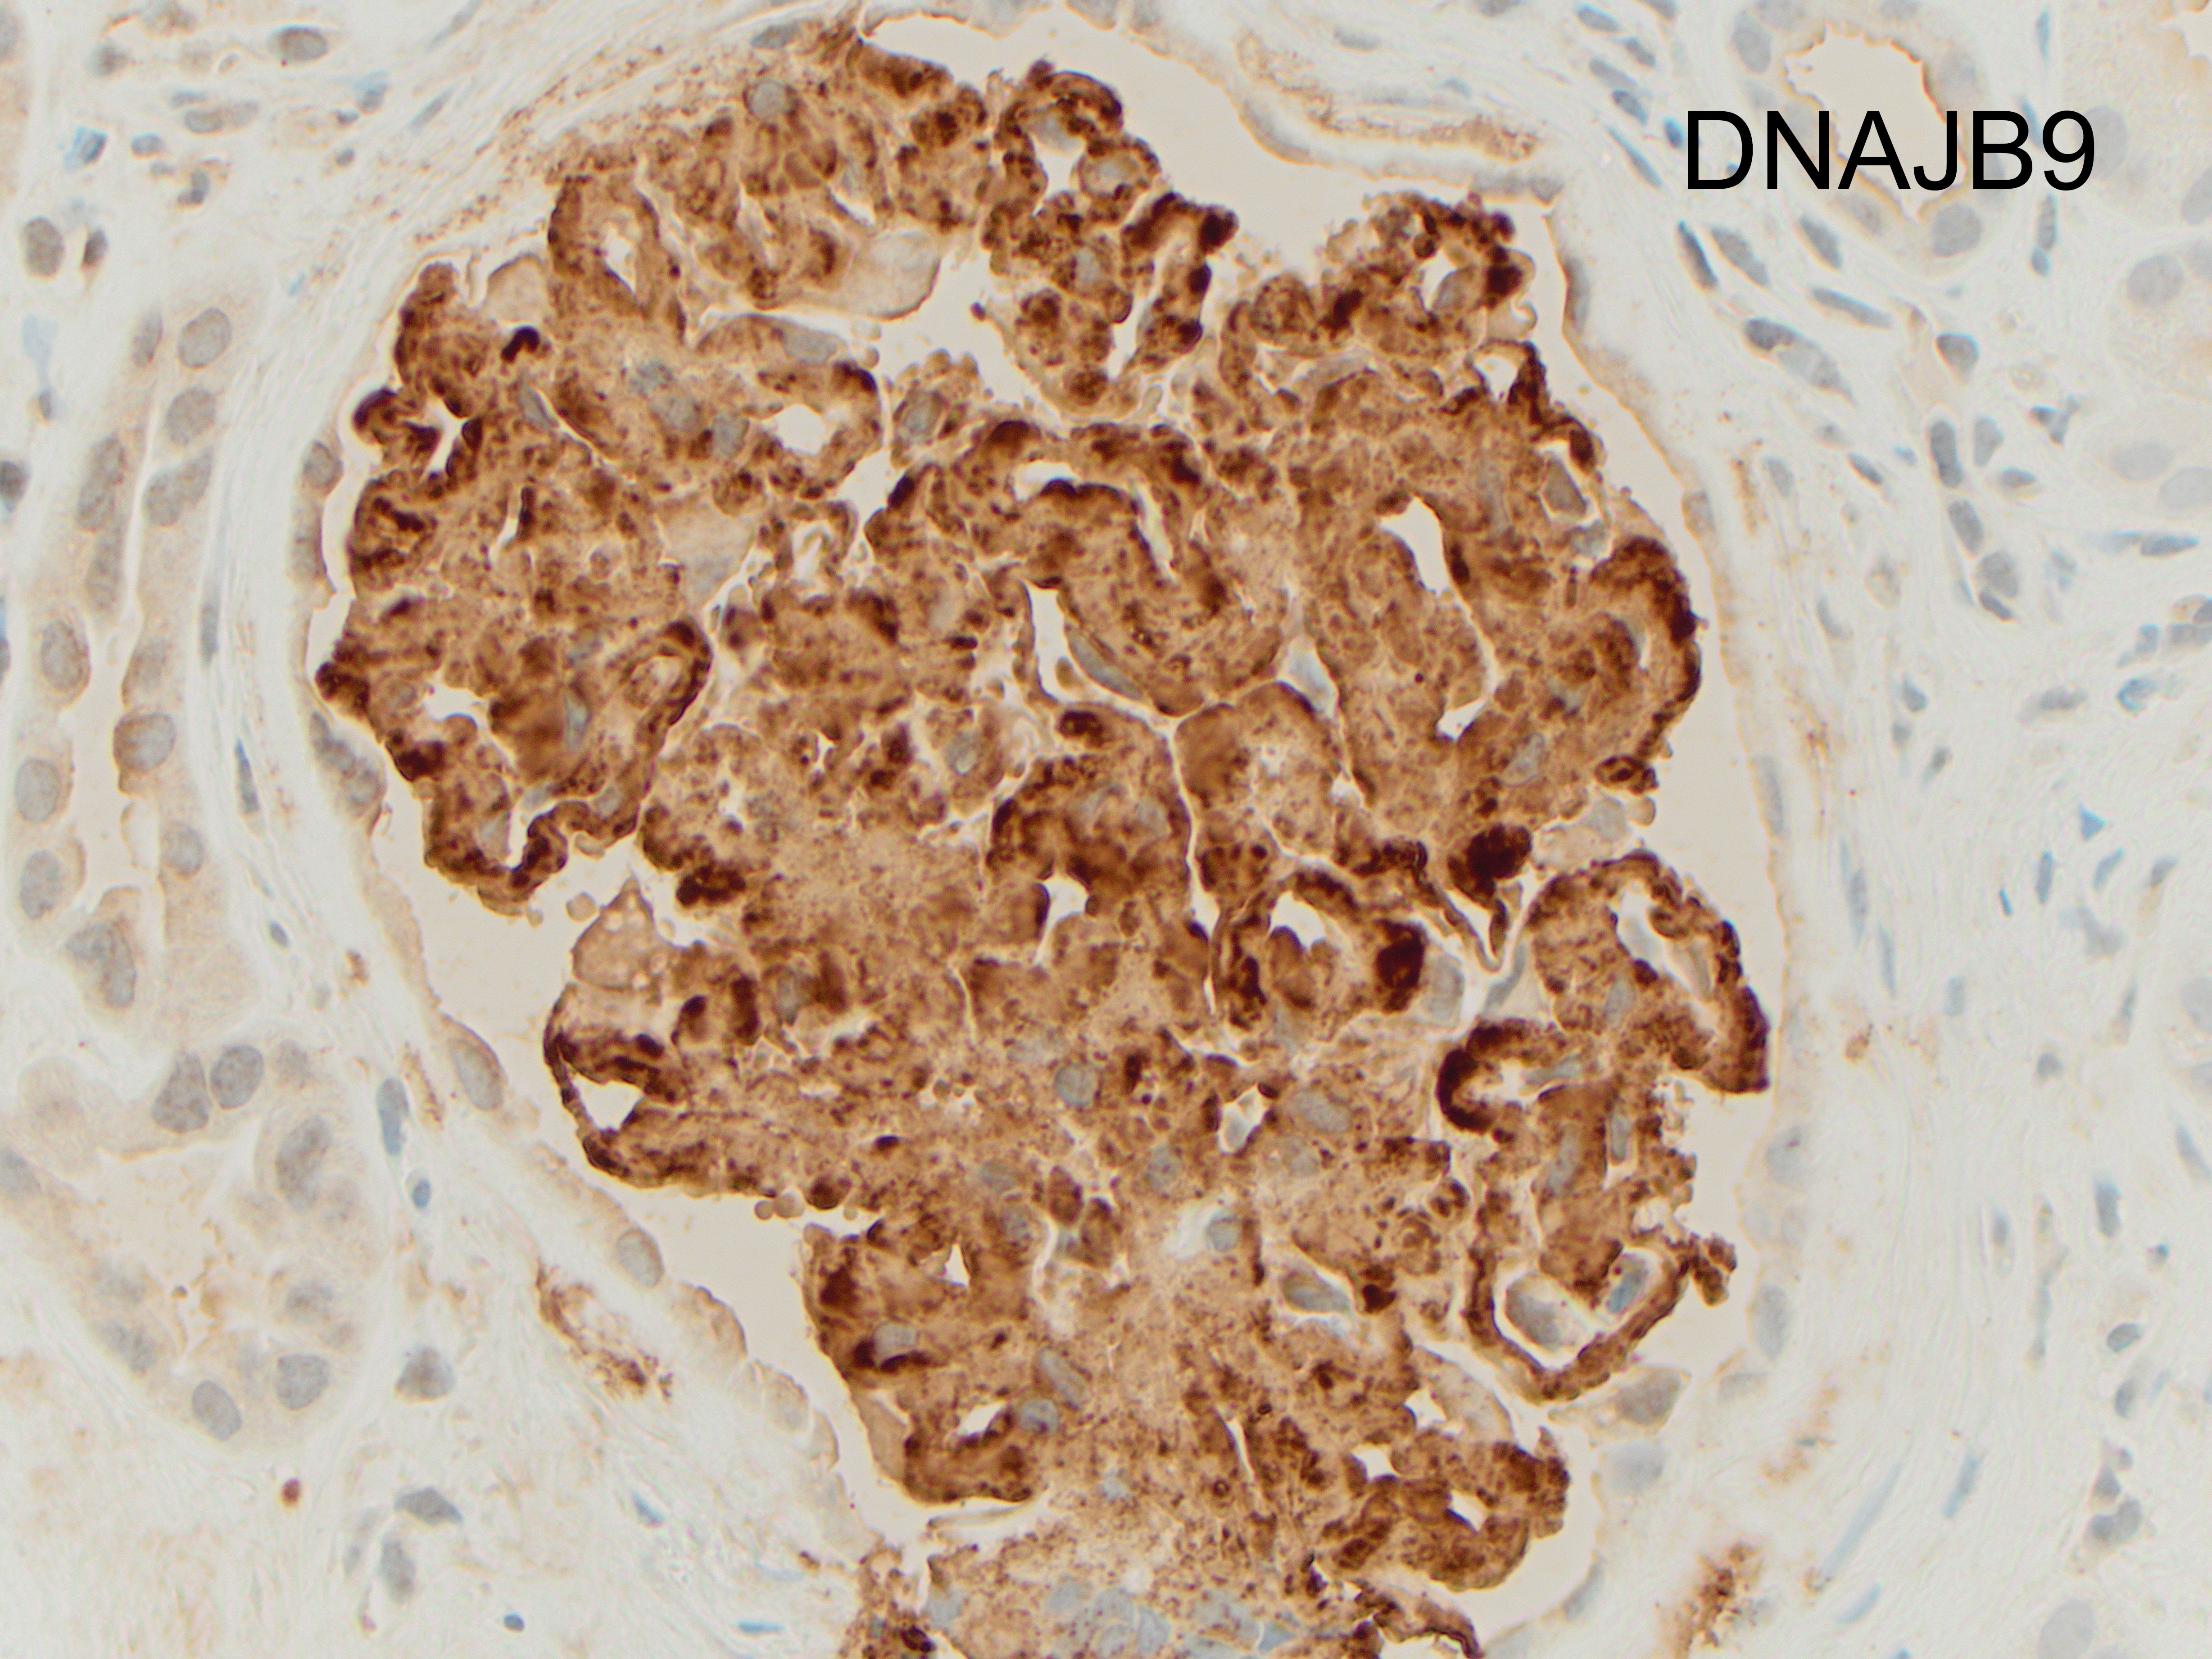

Immunohistochemical staining for DNAJB9 (DnaJ homolog subfamily B member 9) helps confirm the diagnosis of fibrillary glomerulonephritis (FGN) in this case (Figure). DNAJB9 is a member of the DNA-J heat-shock protein family, that act as co-chaperones for the heat shock protein 70 family members, important chaperones in proper folding, translocation, or degradation of proteins. Although DNAJB9 is expressed at low levels in all cell types, FGN is, at present, the only disease that has been shown to be associated with large amounts of extracellular deposition of this protein.

By light microscopy, the most commonly reported patterns of injury are membranoproliferative and mesangial proliferative, with focal crescents in 17-50% of the cases (like in this case which showed less than 50% of glomeruli involved; figure). The deposits result in expansion of the mesangium and/or capillary walls by eosinophilic material that is pale with periodic acid-Schiff, nonargyrophilic, and negative for Congo red. By immunofluorescence, “smudgy” mesangial and/or capillary wall intense staining for IgG (most often IgG4 subclass), usually with C3, kappa and lambda light chains is noted. IgM, IgA and C1q show weaker positive staining in some cases.

The distinction between FGN and amyloidosis is made on the basis of Congo red, DNAJB9 (high sensitivity and specificity for FGN) and composition of fibrils by electron microscopy. Immunohistochemistry against AA amyloid may be used to diagnose a specific type of amyloid deposits. PLA2R (M-type phospholipase-A2 receptor) and THSD7A (thrombospondin type-1 domain-containing 7A) are used in the diagnosis of membranous nephropathy.